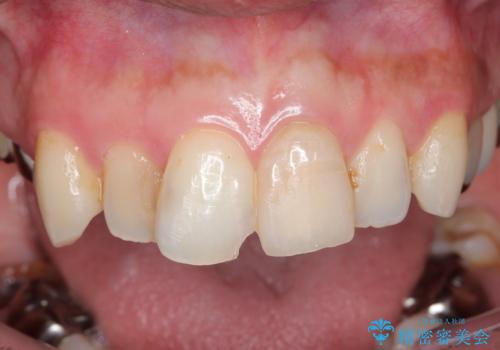

転んで折れた前歯セラミック治療で審美改善

- 自転車で転倒してしまい、前歯を折ってしまい、痛みと見た目の改善を希望され来院されました。

もともと根管治療の為されて歯が折れてしまっているので、根管治療を行い審美的なセラミック治療を行う治療計画としました。

周囲の歯と調和した審美的な仕上がりに満足いただくことができました。